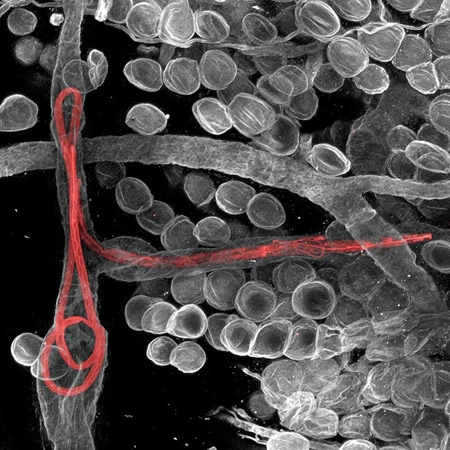

Giun ký sinh có màu đỏ sống trong các tế bào bạch huyết tai của con chuột. Ảnh chụp bởi tiến sĩ Witold Kilarski, phòng thực nghiệm bạch huyết và ung thư EPFL, Lausanne, Thụy Sĩ.